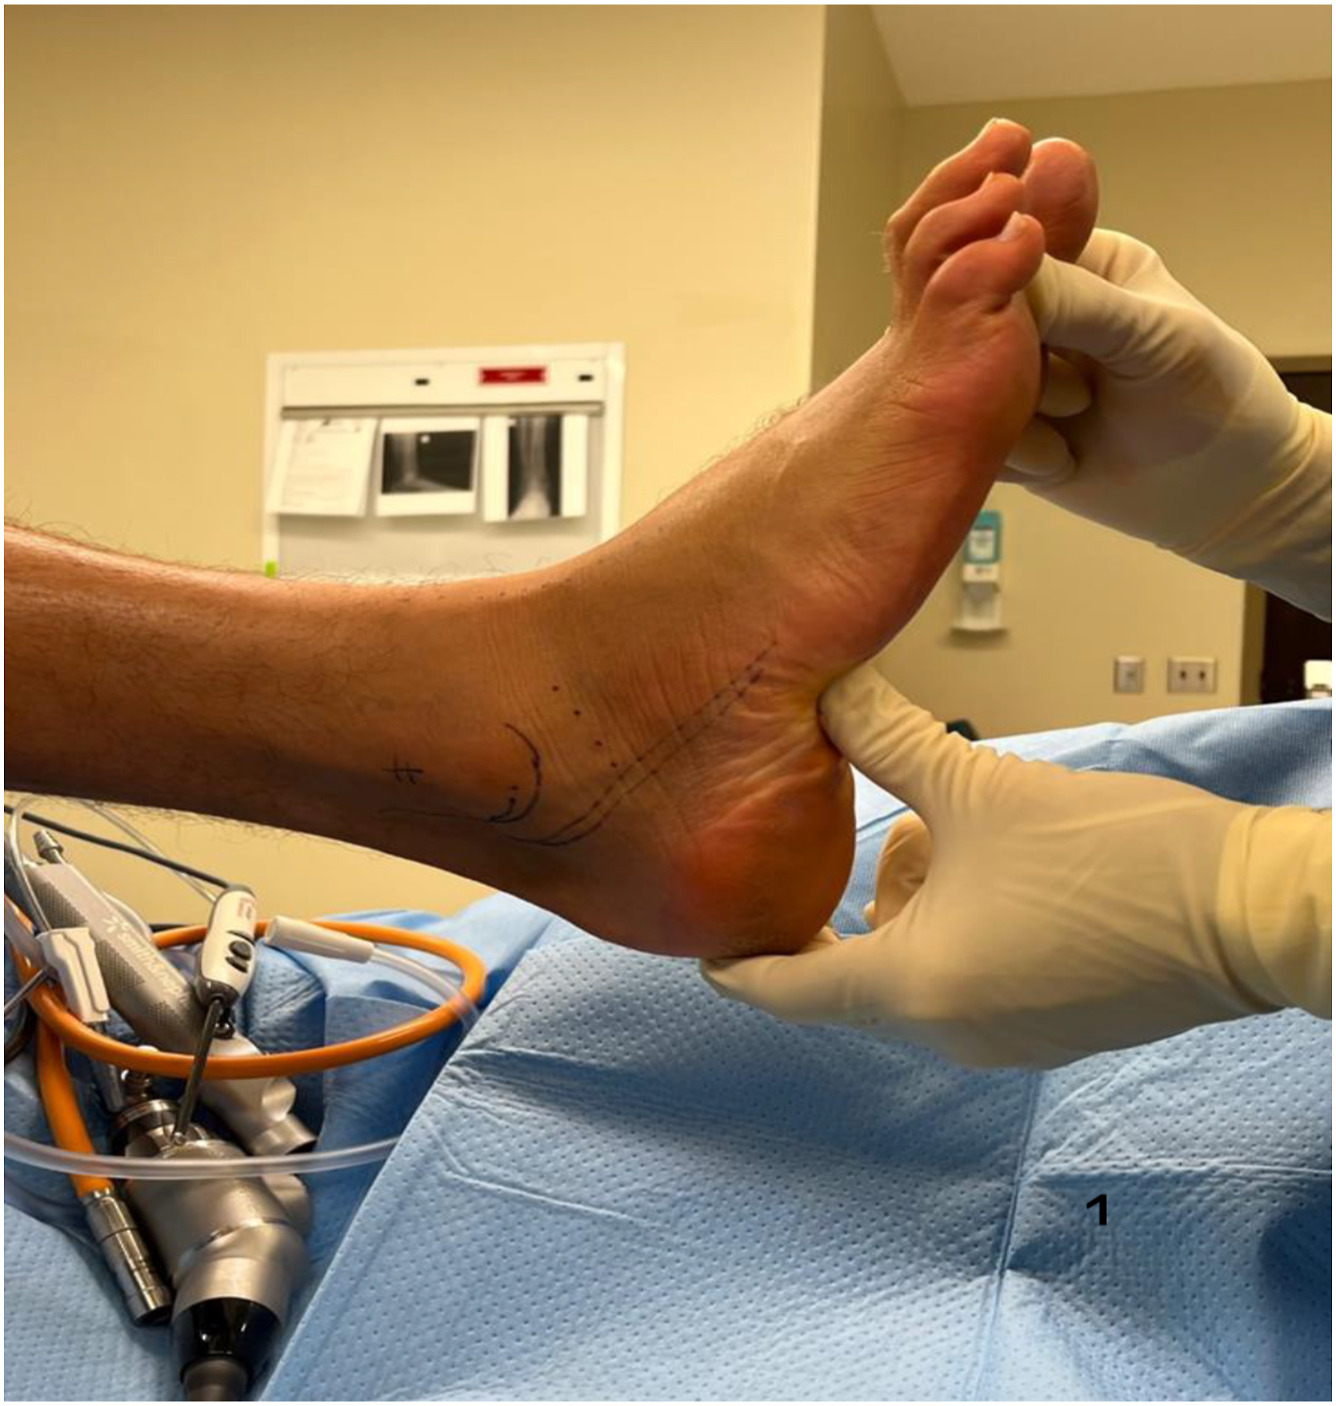

Achilles Tendon Reconstruction

Repairs damaged tendon to restore strength and function.